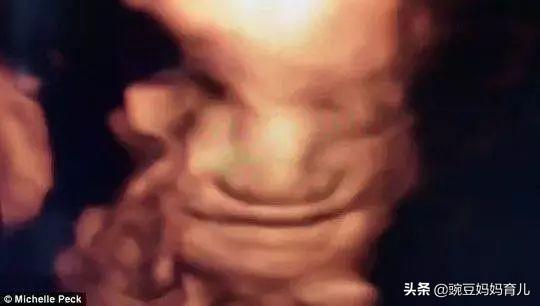

先看1张图片,图片是2010年英国医学家公布的17个周大胎儿在妈妈肚子里微笑的照片,特别震撼。因为这张照片,被认为17个周大的胎儿已经感知到快乐与痛苦,17个周以后还流产是非常不人道的。

看上图,B超显示下,胎儿笑的多可爱!

怀孕五个半月,胎儿会笑吗?为什么?22周已经可以做四维排畸检查了(建议22周~26周),如果宝宝比较配合,可以看到他笑的样子并且拍下来做纪念。上面这张图就是一位粉丝妈妈提供的,最后一副是宝宝笑的样子。